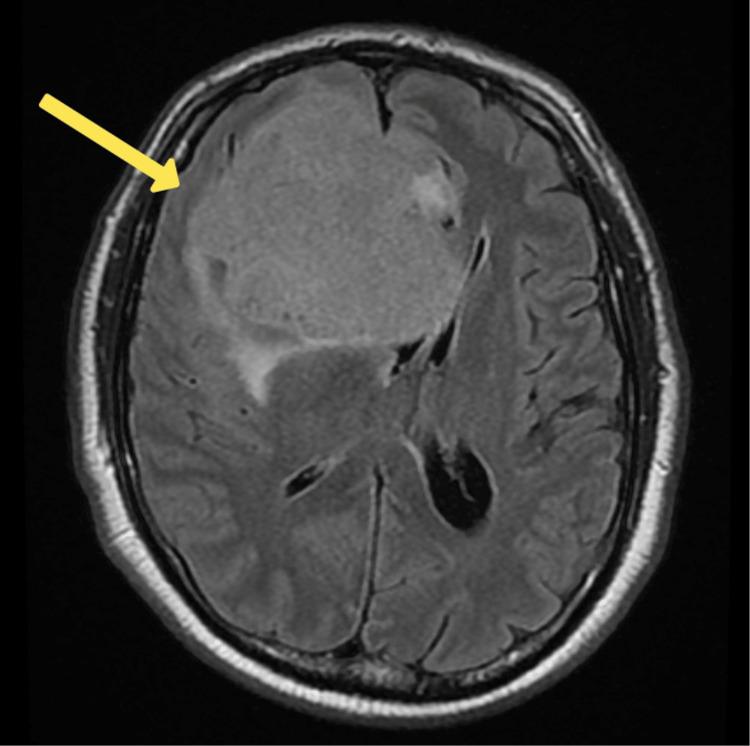

The exclusion of organic causes for psychiatric symptoms is a routine practice in mental healthcare. Brain tumors can elicit a range of mood, behavioral, or cognitive symptoms that mimic mental health disorders, significantly altering a patient's personality and behavior if left undiagnosed or untreated. This case report presents a 56-year-old Middle Eastern male with no prior history of mental illness who exhibited a three-week history of depressive symptoms, social withdrawal, and poor self-care. Despite treatment, his condition deteriorated, manifesting psychomotor retardation, urinary incontinence, paranoia, mood lability, and sexually disinhibited behavior. Neuroimaging revealed a large extra-axial mass in the anterior cranial fossa, indicative of a meningioma, necessitating referral to neurosurgery. CT and MRI scans confirmed a hyperdense mass lesion (7.1 x 7.7 x 7.5 cm), causing structural erosion and a midline shift. This case underscores the importance of considering organic causes in atypical psychiatric presentations. Meningiomas, particularly those in the frontal lobes, can present primarily with psychiatric symptoms, complicating early diagnosis. Neuroimaging is critical for accurate diagnosis and effective management in such cases. Clinicians should be vigilant for organic causes in patients with atypical psychiatric symptoms, especially in those over 50. Early neuroimaging can lead to timely diagnosis and treatment, significantly improving patient outcomes.

在精神卫生保健中,排除精神症状的器质性病因是一种常规做法。脑肿瘤可引发一系列情绪、行为或认知症状,这些症状酷似精神健康障碍,如果未被诊断或治疗,会显著改变患者的性格和行为。本病例报告介绍了一名56岁的中东男性,他既往无精神疾病史,出现了为期三周的抑郁症状、社交退缩和自我照料不佳的情况。尽管接受了治疗,他的病情仍恶化,表现出精神运动迟缓、尿失禁、妄想、情绪不稳定和性抑制行为。神经影像学检查显示颅前窝有一个巨大的轴外肿块,提示为脑膜瘤,需要转诊至神经外科。CT和MRI扫描证实有一个高密度肿块病变(7.1×7.7×7.5厘米),导致结构侵蚀和中线移位。本病例强调了在非典型精神症状表现中考虑器质性病因的重要性。脑膜瘤,尤其是额叶的脑膜瘤,可能主要表现为精神症状,使早期诊断复杂化。在此类病例中,神经影像学检查对于准确诊断和有效管理至关重要。临床医生应对有非典型精神症状的患者,尤其是50岁以上的患者警惕器质性病因。早期神经影像学检查可实现及时诊断和治疗,显著改善患者预后。